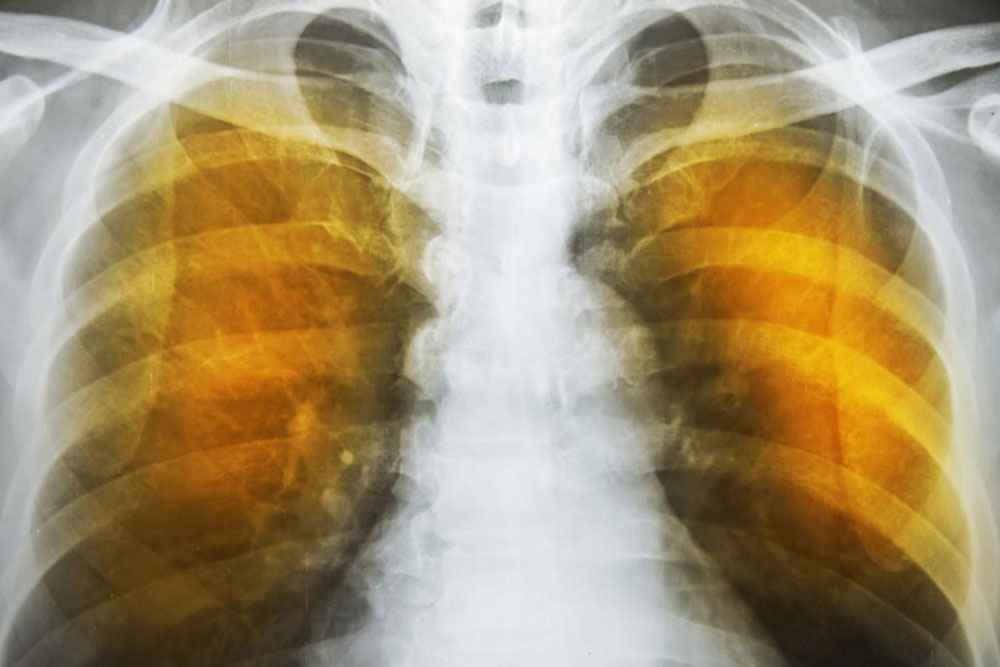

The next reaction is to cough out the irritants and the mucus. Severe forceful coughs can raise the pressure in the alveoli considerably and can rupture their exceedingly thin walls. The reduction of area for gas transfer and the loss of elastic tissues in the lungs reduces the capacity of the lungs to expel air. This reduces the intake volume of fresh air during breathing and can also lead to infections. These conditions produce the characteristic symptoms of wheezing, tightness in chest, labored breathing and coughing. These are also indications as well as symptoms of severe asthma.

The symptoms of emphysema are exceedingly severe and cause considerable damage to the lungs before the symptoms even show up. Generally, one feels a lack of energy and the tendency to skip some of the common daily routines. It progresses from slight difficulty in breathing to wheezing and then to a persistent cough that does not go away. One starts to feel a tightness in the chest and feels short of breath on exertion. Tiredness and persistent cough become constant.

As the deterioration continues, the alveoli lose their strength and start rupturing. In extreme cases, there may be large scale destruction which leads to empty spaces in lungs called bullae. This would reduce the functional area of the lung which in extreme cases call for surgical removal. In an extremely rare condition, large scale rupture of alveoli can cause a condition called pneumothorax and the collapse of the lung, a very serious condition, which can be fatal. The best thing one can do is stop exposure to irritants.